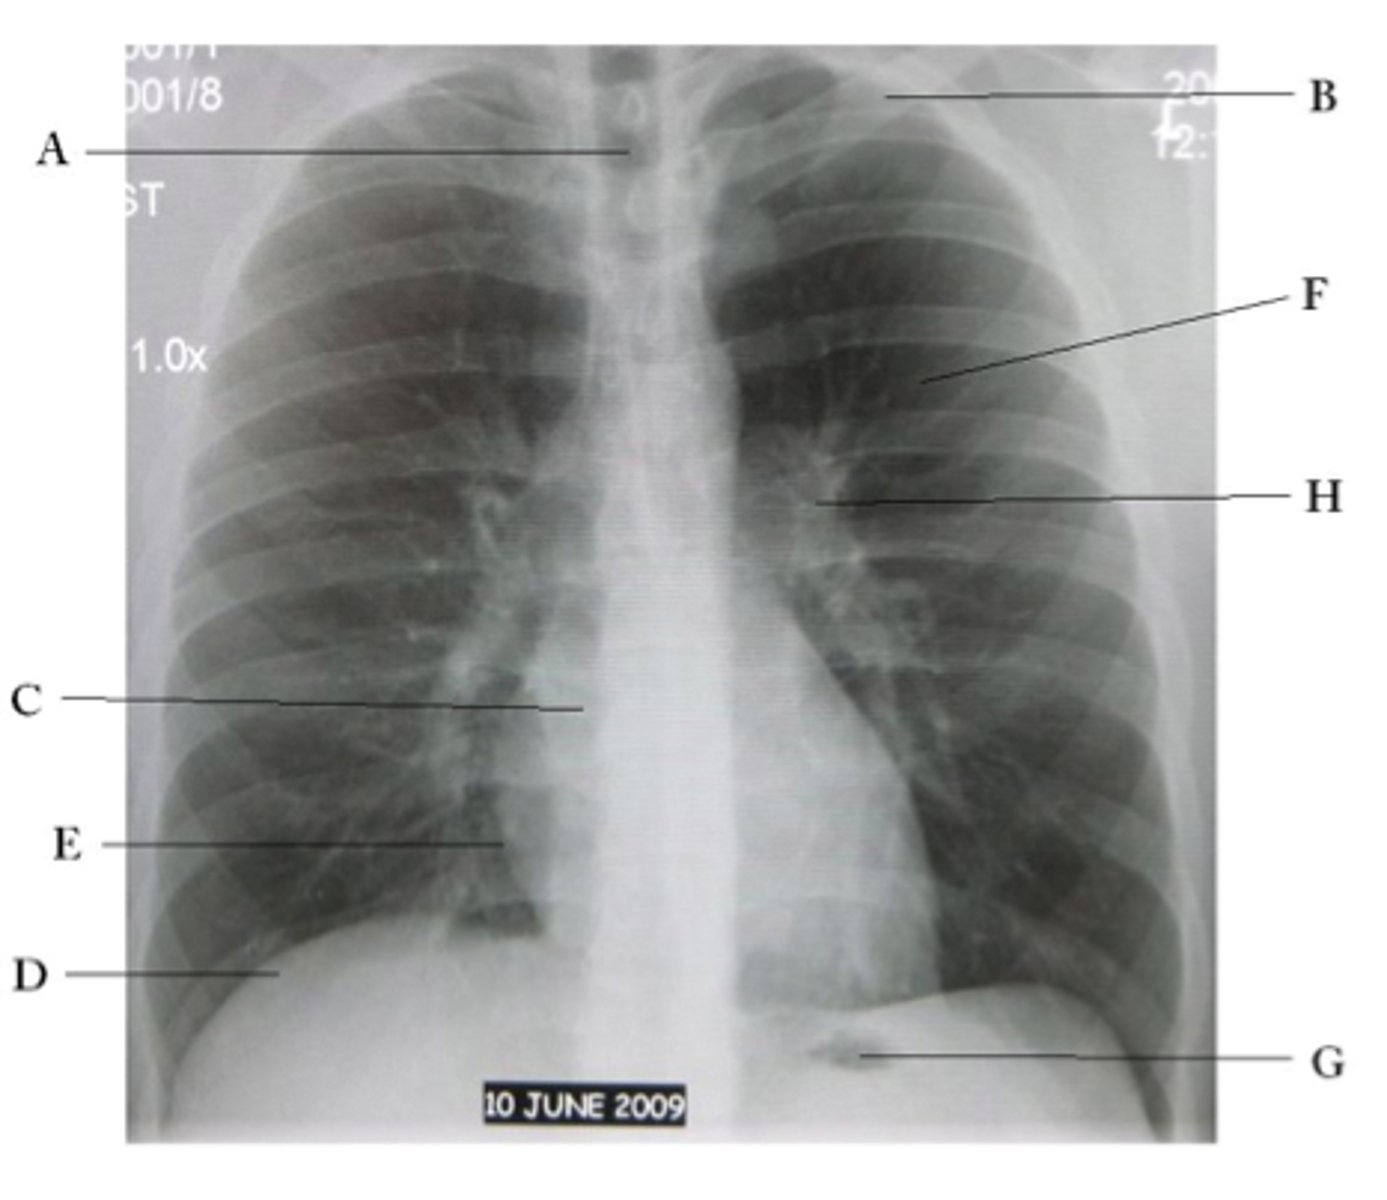

A

trachea

B

Clavicle

C

Right atrium

D

Diaphragm

E

Cardiophrenic angle

F

left upper lobe

G

gastric bubble

H

Left hilum